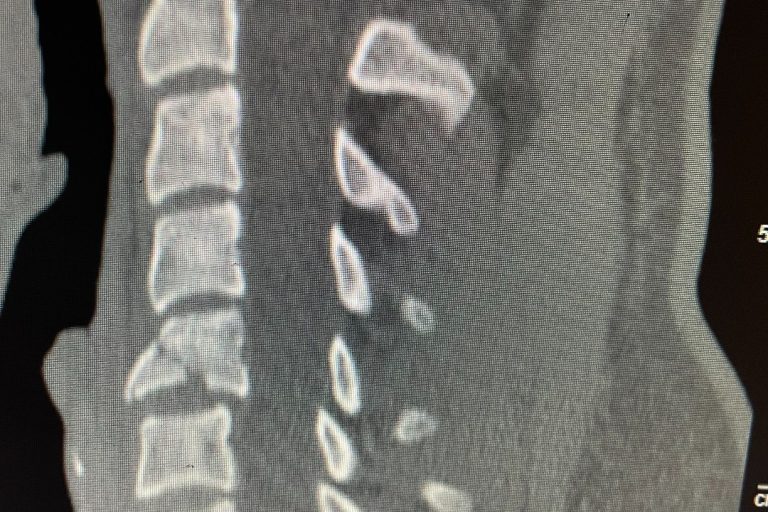

Cervical total disc replacement or disc arthroplasty is becoming an increasingly popular procedure. Now, the cervical disc replacements are even approved for doing 2 levels, as in this recent case that I performed. Is it right for you? Many things are possible in spine surgery but only a few things are most appropriate for you…